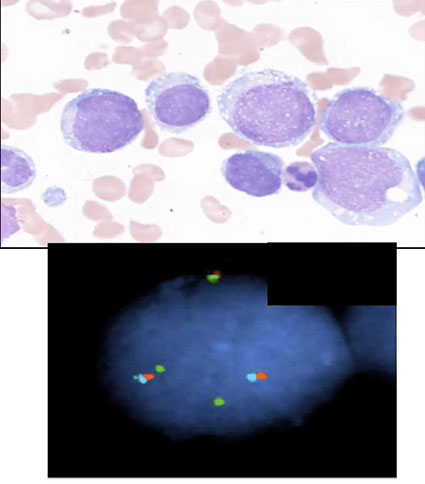

CML- chronic phase PB

CML: FISH major breakpoint; Red=ABL, Green = BCR

CML - dwarf megs